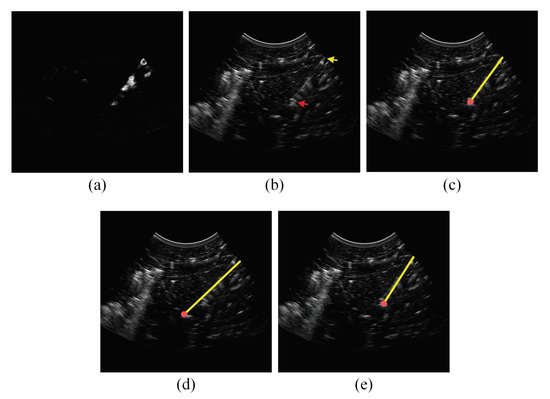

2.2. Analyzing the Power Doppler Ultrasound Image to Obtain an Initial Estimation of the Needle Axis and Identify the Candidate Regions of the Needle

2.3. Analyzing the B-Mode Ultrasound Image to Obtain Accurate Localization of the Needle Axis

2.4. Analyzing the Power Doppler and B-Mode Ultrasound Images to Obtain Accurate Localization of the Needle Tip